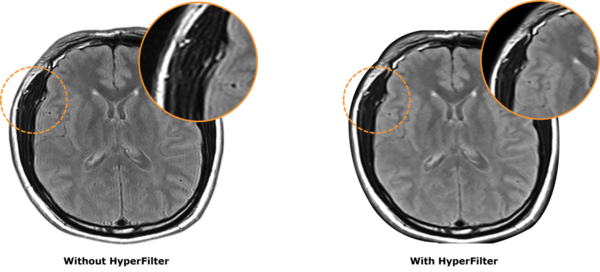

Hyper.Filter

Giúp giảm nhiễu và giả ảnh, nâng cao độ chính xác trong chẩn đoán